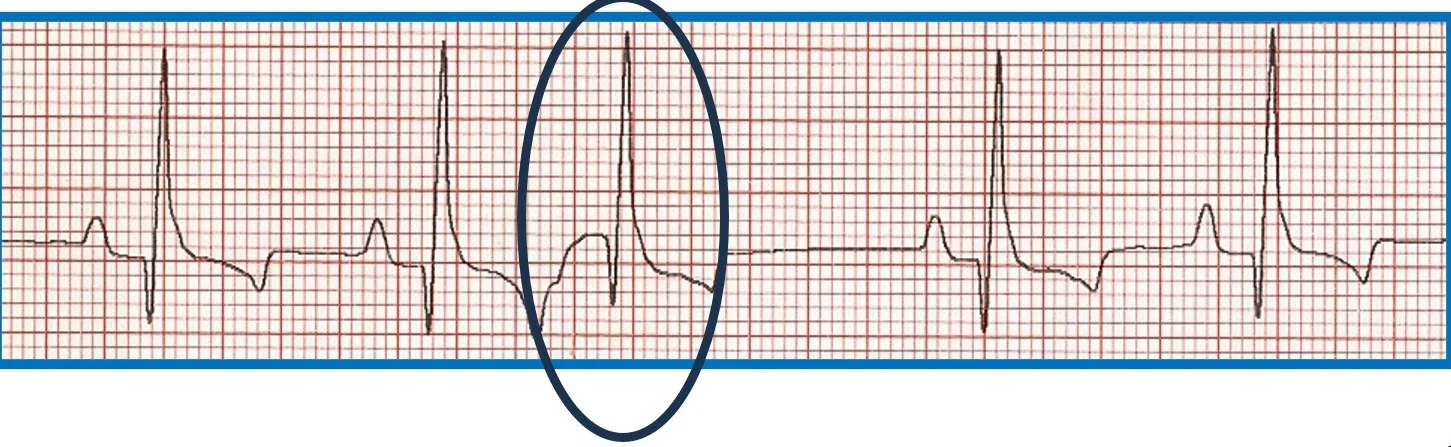

Premature beats originating at or above the AV junction can still be rapidly conducted to the ventricular myocardium via specialized conduction tissue and therefore appear nearly identical to the regular rhythm. Premature beats originating below the AV junction (ie, below the bundle of His) cannot use the specialized conduction system and must therefore depolarize the ventricles via muscle cell to muscle cell conduction. This is a relatively slow process that produces a wide, bizarre QRS complex that can be predominantly positive or negative depending on where and in which ventricle the impulse starts and what direction it travels from to allow for complete ventricular depolarization. There will not be a related P wave because the impulse forms and depolarizes independently from atrial depolarization. Because depolarization is abnormal, repolarization is also abnormal and is represented by a large, bizarre T wave on ECG (Figure 6).

FIGURE 6 Effect of ectopic foci origination location on ECG appearance. (A) ECG showing a normal QRS complex but indiscernible P wave (circle) characteristic of premature beats with supraventricular origin; the circled premature beat is almost identical to the beats with an associated P wave. (B) Illustration demonstrating where ectopic foci result in supraventricular (above dotted line) and ventricular (below dotted line) ECG patterns. (C) ECG showing no P wave; a wide, bizarre QRS complex; and a large, bizarre T wave (circles) characteristic of premature beats with a ventricular origin.